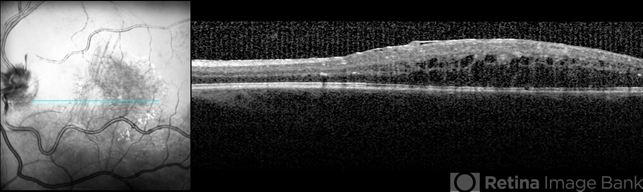

- Optic coherence tomography of a 31-year-old man with idiopathic retinitis, vasculitis, aneurysms and neuro-retinitis (IRVAN) syndrome.